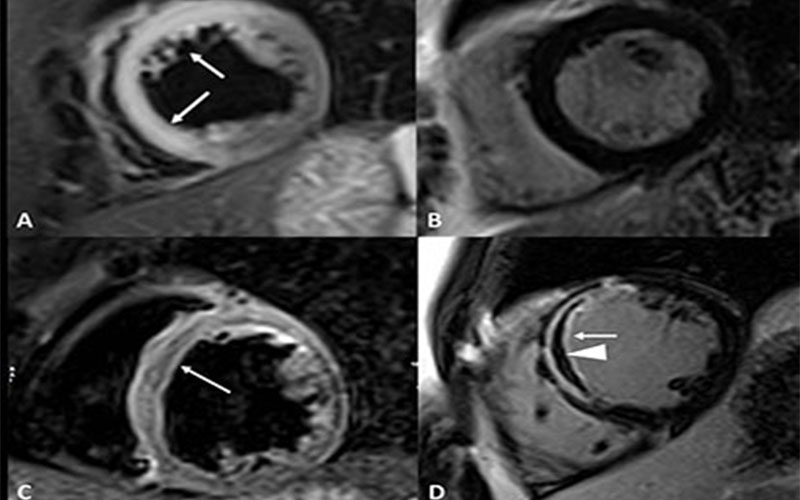

DeRubeis Figure 2

MR images of aborted myocardial infarction in a 44-year-old woman with acute chest pain, chronic cocaine abuse (>10 years), troponin elevation, and ST elevation at admission electrocardiography.